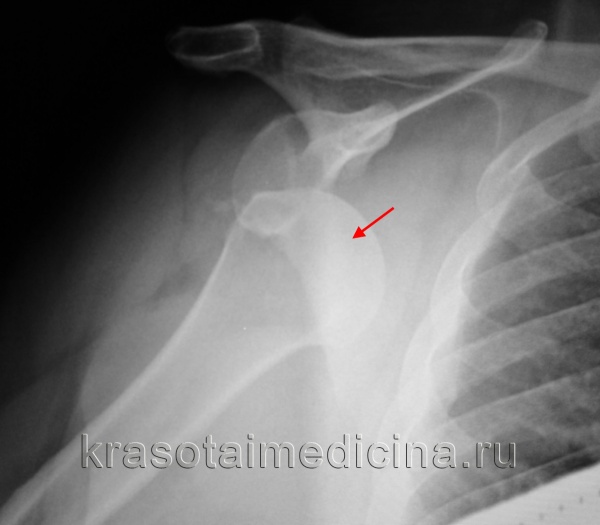

На фото нижи- дефект Банкарта и Хилла-Сакса в положении вывиха.

Рентгенография при вывихе плеча

image

Рентгенография плечевого сустава. Вывих головки правой плечевой кости из суставной ямки.